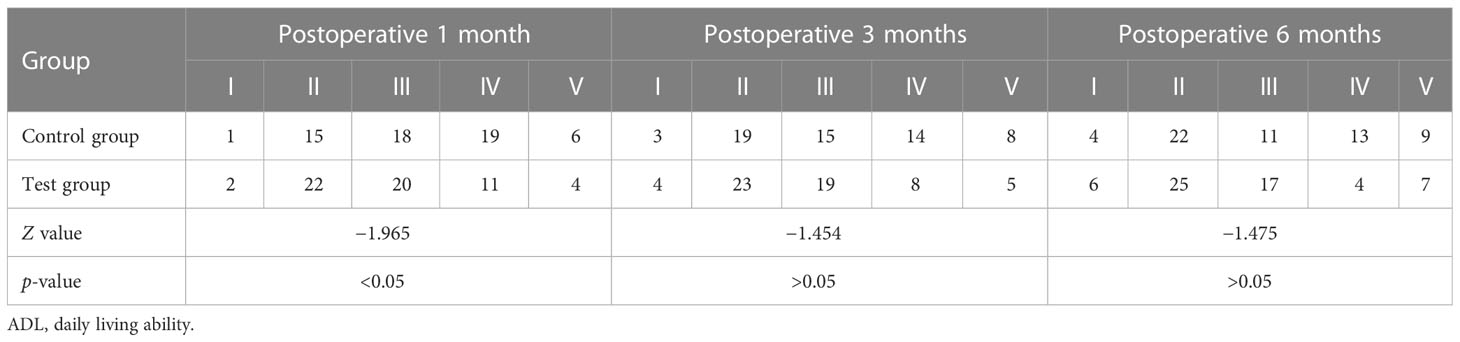

3.2 Comparison of ADL grading evaluation results between the two groups at 1, 3, and 6 months postoperatively

One month postoperatively, the ADL grading of the patients in the test group was significantly better than that in the control group (p < 0.05), and the recovery of patients in the test group was also better than that in the control group.

However, at 3 and 6 months postoperatively, there was no significant difference in the ADL grading between the two groups (p > 0.05) Table 2), although there were more patients in the test group who recovered well (Grade I to Grade III) than those in the control group.

Results: The hematoma clearance rates of the group using 3D laser combined with C-arm CT at 3, 5, and 7 days after surgery were significantly higher than those of the control group, and the difference was statistically significant (p < 0.05). One month postoperatively, the daily living ability (ADL) grading and recovery of the patients in the test group was significantly better than those of the control group (p < 0.05), but there was no statistically significant difference in ADL 3 and 6 months after surgery (p > 0.05).